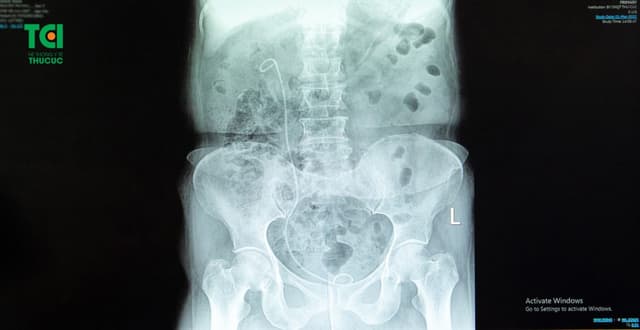

Đặt ống sonde jj niệu quản trong điều trị sỏi tiết niệu

Đặt ống sonde JJ là một là một trong những bước quan trọng cho người bệnh trong điều trị sỏi tiết niệu. Hãy cùng tìm hiểu kỹ về quá trình đặt ống sonde JJ niệu quản được sử dụng khi nào, mang đến lợi ích gì cho người bệnh, và những lưu ý về tác […]